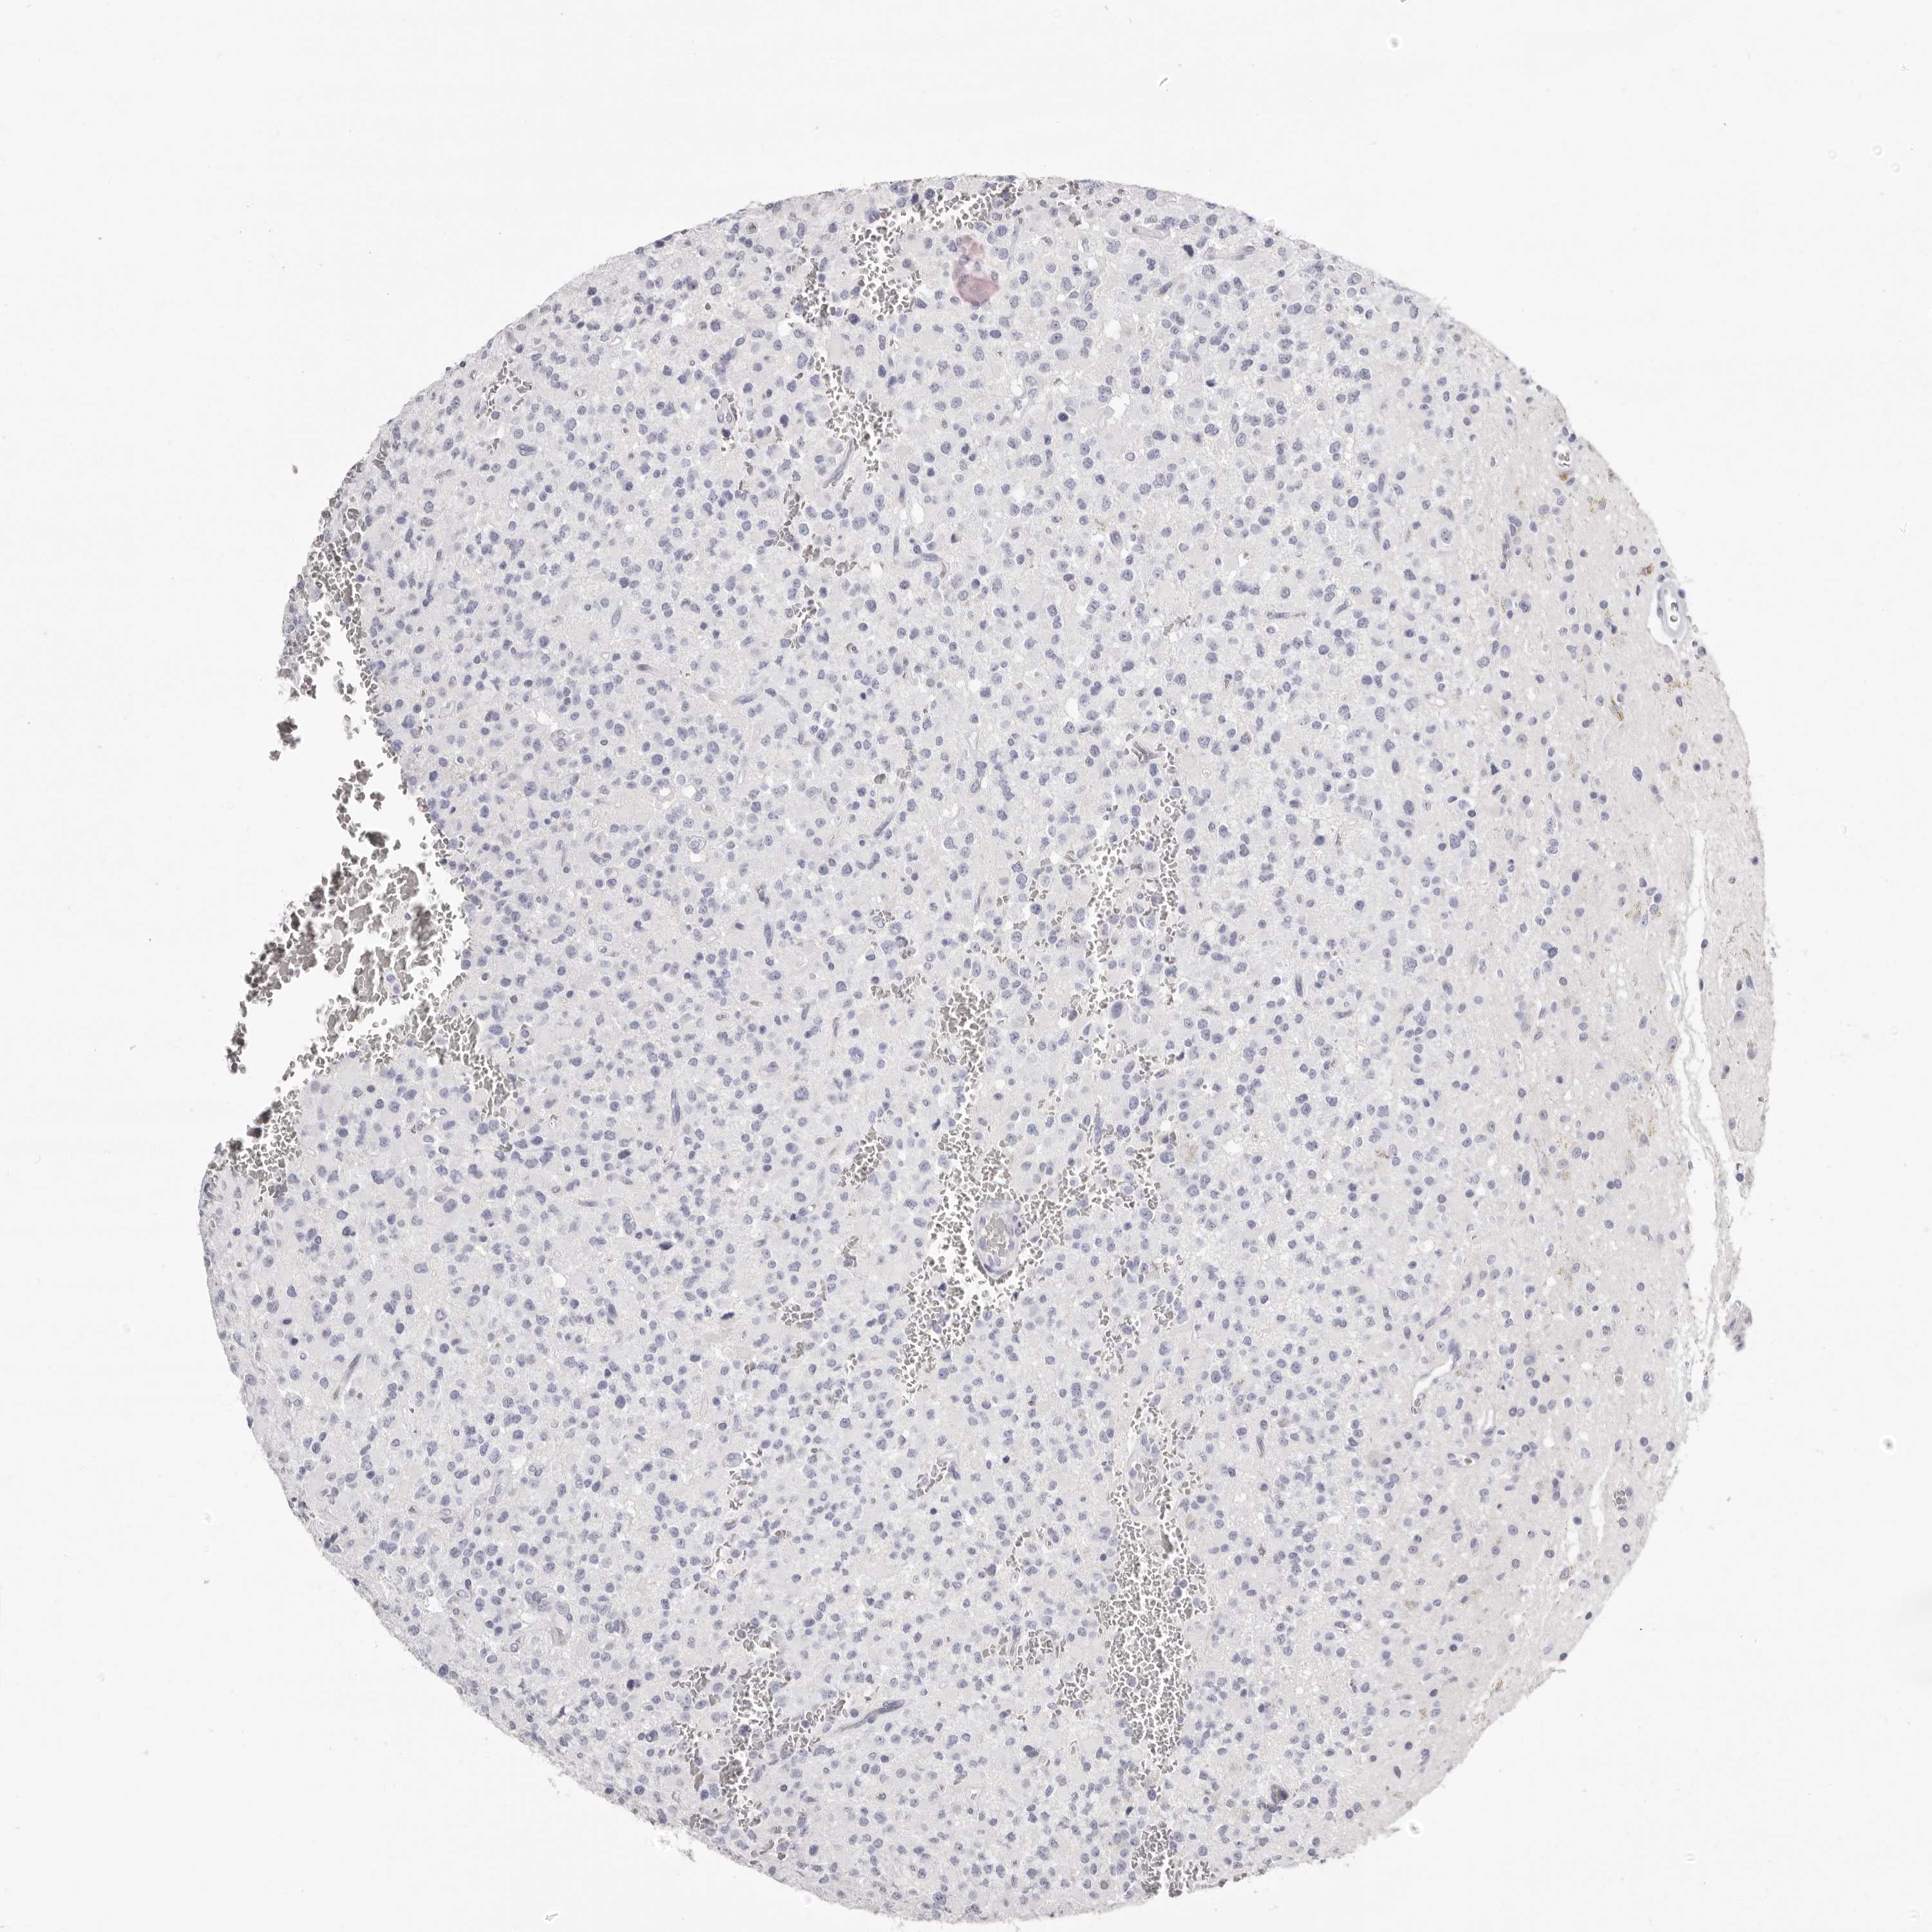

GLIOMA - Protein expressioni

A mouse-over function shows sample information and annotation data. Click on an image to view it in a full screen mode. Samples can be filtered based on level of antibody staining by selecting one or several of the following categories: high, medium, low and not detected. The assay and annotation is described here.

Note that samples used for immunohistochemistry by the Human Protein Atlas do not correspond to samples in the TCGA dataset.

Antibody stainingi

Antibody staining in the annotated cell types in the current human tissue is reported as not detected, low, medium, or high, based on conventional immunohistochemistry profiling in selected tissues. This score is based on the combination of the staining intensity and fraction of stained cells.

Each image is clickable and will lead to virtual microscopy that enables deeper exploration of all samples and also displays staining intensity scores, fraction scores and subcellular localization as well as patient and tissue information for each sample.

Antibody HPA028688

Staining

High

Medium

Low

Not detected

Intensity

Strong

Moderate

Weak

Negative

Quantity

>75%

75%-25%

<25%

None

Location

Nuclear

Cytoplasmic/membranous

Cytoplasmic/membranous,nuclear

Glioma, malignant, High grade

Glioma, malignant, Low grade

Glioblastoma, NOS